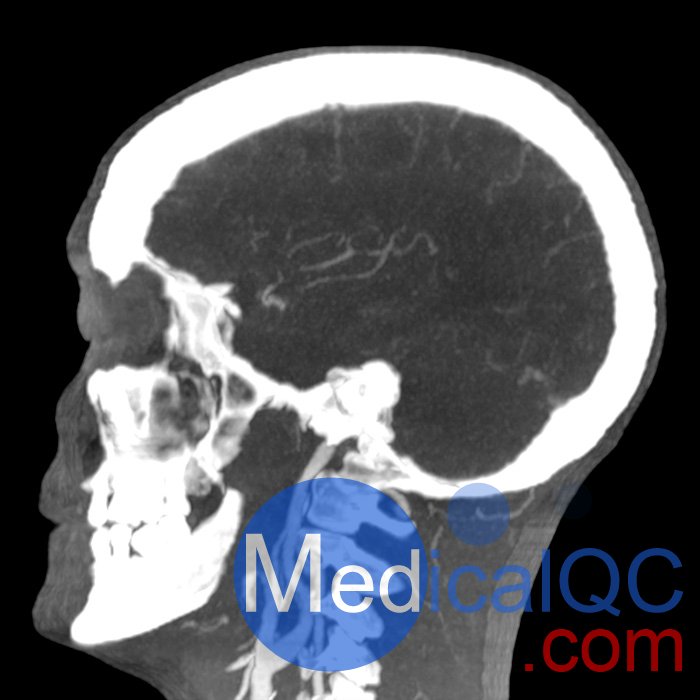

phantomX頭部模體具有逼真解剖結構的頭頸部模體

頭頸部體模提供逼真的解剖結構,旨在模擬計算機斷層掃描、X 射線成像和放射治療中的臨床成像。這些模型在定義的能譜下提供了所有組織的真實模擬和真實的衰減值。

phantomX頭頸部模型,phantomX頭部模體是根據 CT 數據制造的,包括所有組織的解剖細節。它經過優化,可在計算機斷層掃描中以 120 kVp 成像提供真實的衰減值,對應于 73 keV 的平均光譜能量。可根據要求校準其他光譜能量。

體模的尺寸和設計可能會發生細微變化。體模可以作為一件式擬人體模或以截面設計的形式提供。可以包括病理特征(例如,腫塊、血管病變)。